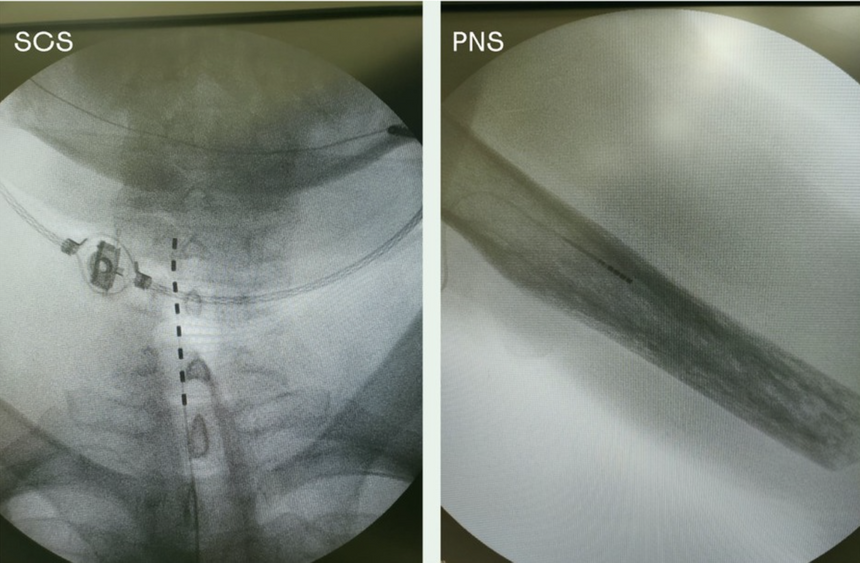

В эксперименте принимали участие два пациента с ампутацией на уровне плеча, которым были имплантированы электроды в спинной мозг и периферический нерв. Суть исследования заключалась в сравнении этих двух видов стимуляции, чтобы выяснить, какой из них более естественно воспринимается мозгом. Результаты показали, что стимуляция периферического нерва вызывает более точечные ощущения, которые больше напоминают естественные тактильные реакции.

Рентгеновский снимок электродов, имплантированных одному из участников эксперимента.